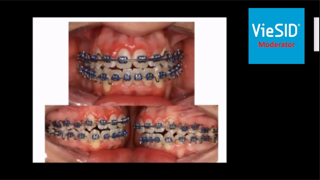

左下が今回のプレゼンテーション症例、右下が当院で行われた矯正治療症例です。

まず、先生の提示されたケースにおいては通法通り矯正器具とゴムによる牽引で前歯が閉鎖されているのが分かりますね。

矯正治療には「顎間ゴム」という弾性ゴムを装着するのがスタンダードになります。

上下の歯にゴムを付ける事(診断によってゴム位置は変わります)で顎を閉じさせる効果があります。